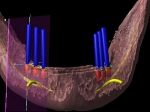

術前術前主訴-総入れ歯の安定が悪い 即時加重可能のミニインプラント使用した。 術前レントゲン術前レントゲン術前レントゲン CT撮影から3次元骨モデルを作成CT撮影から3次元骨モデルを作成CT撮影から3次元骨モデルを作成し埋入位置の確認 フィクスチャーを浸潤麻酔下で埋入フィクスチャーを浸潤麻酔下で埋入。歯茎を切らないので患者さんも非常に楽

4本埋入終了4本埋入終了4本埋入終了(このシステムは4本が絶対条件) 義歯の調整義歯の調整当日に義歯の調整に取りかかる。裏側より義歯をくりぬき維持部のカバー(ハウジング)を義歯の内面に埋め込む step1 義歯の調整義歯の調整当日に義歯の調整に取りかかる。裏側より義歯をくりぬき維持部のカバー(ハウジング)を義歯の内面に埋め込む step2 義歯の調整当日に義歯の調整に取りかかる。裏側より義歯をくりぬき維持部のカバー(ハウジング)を義歯の内面に埋め込む step3